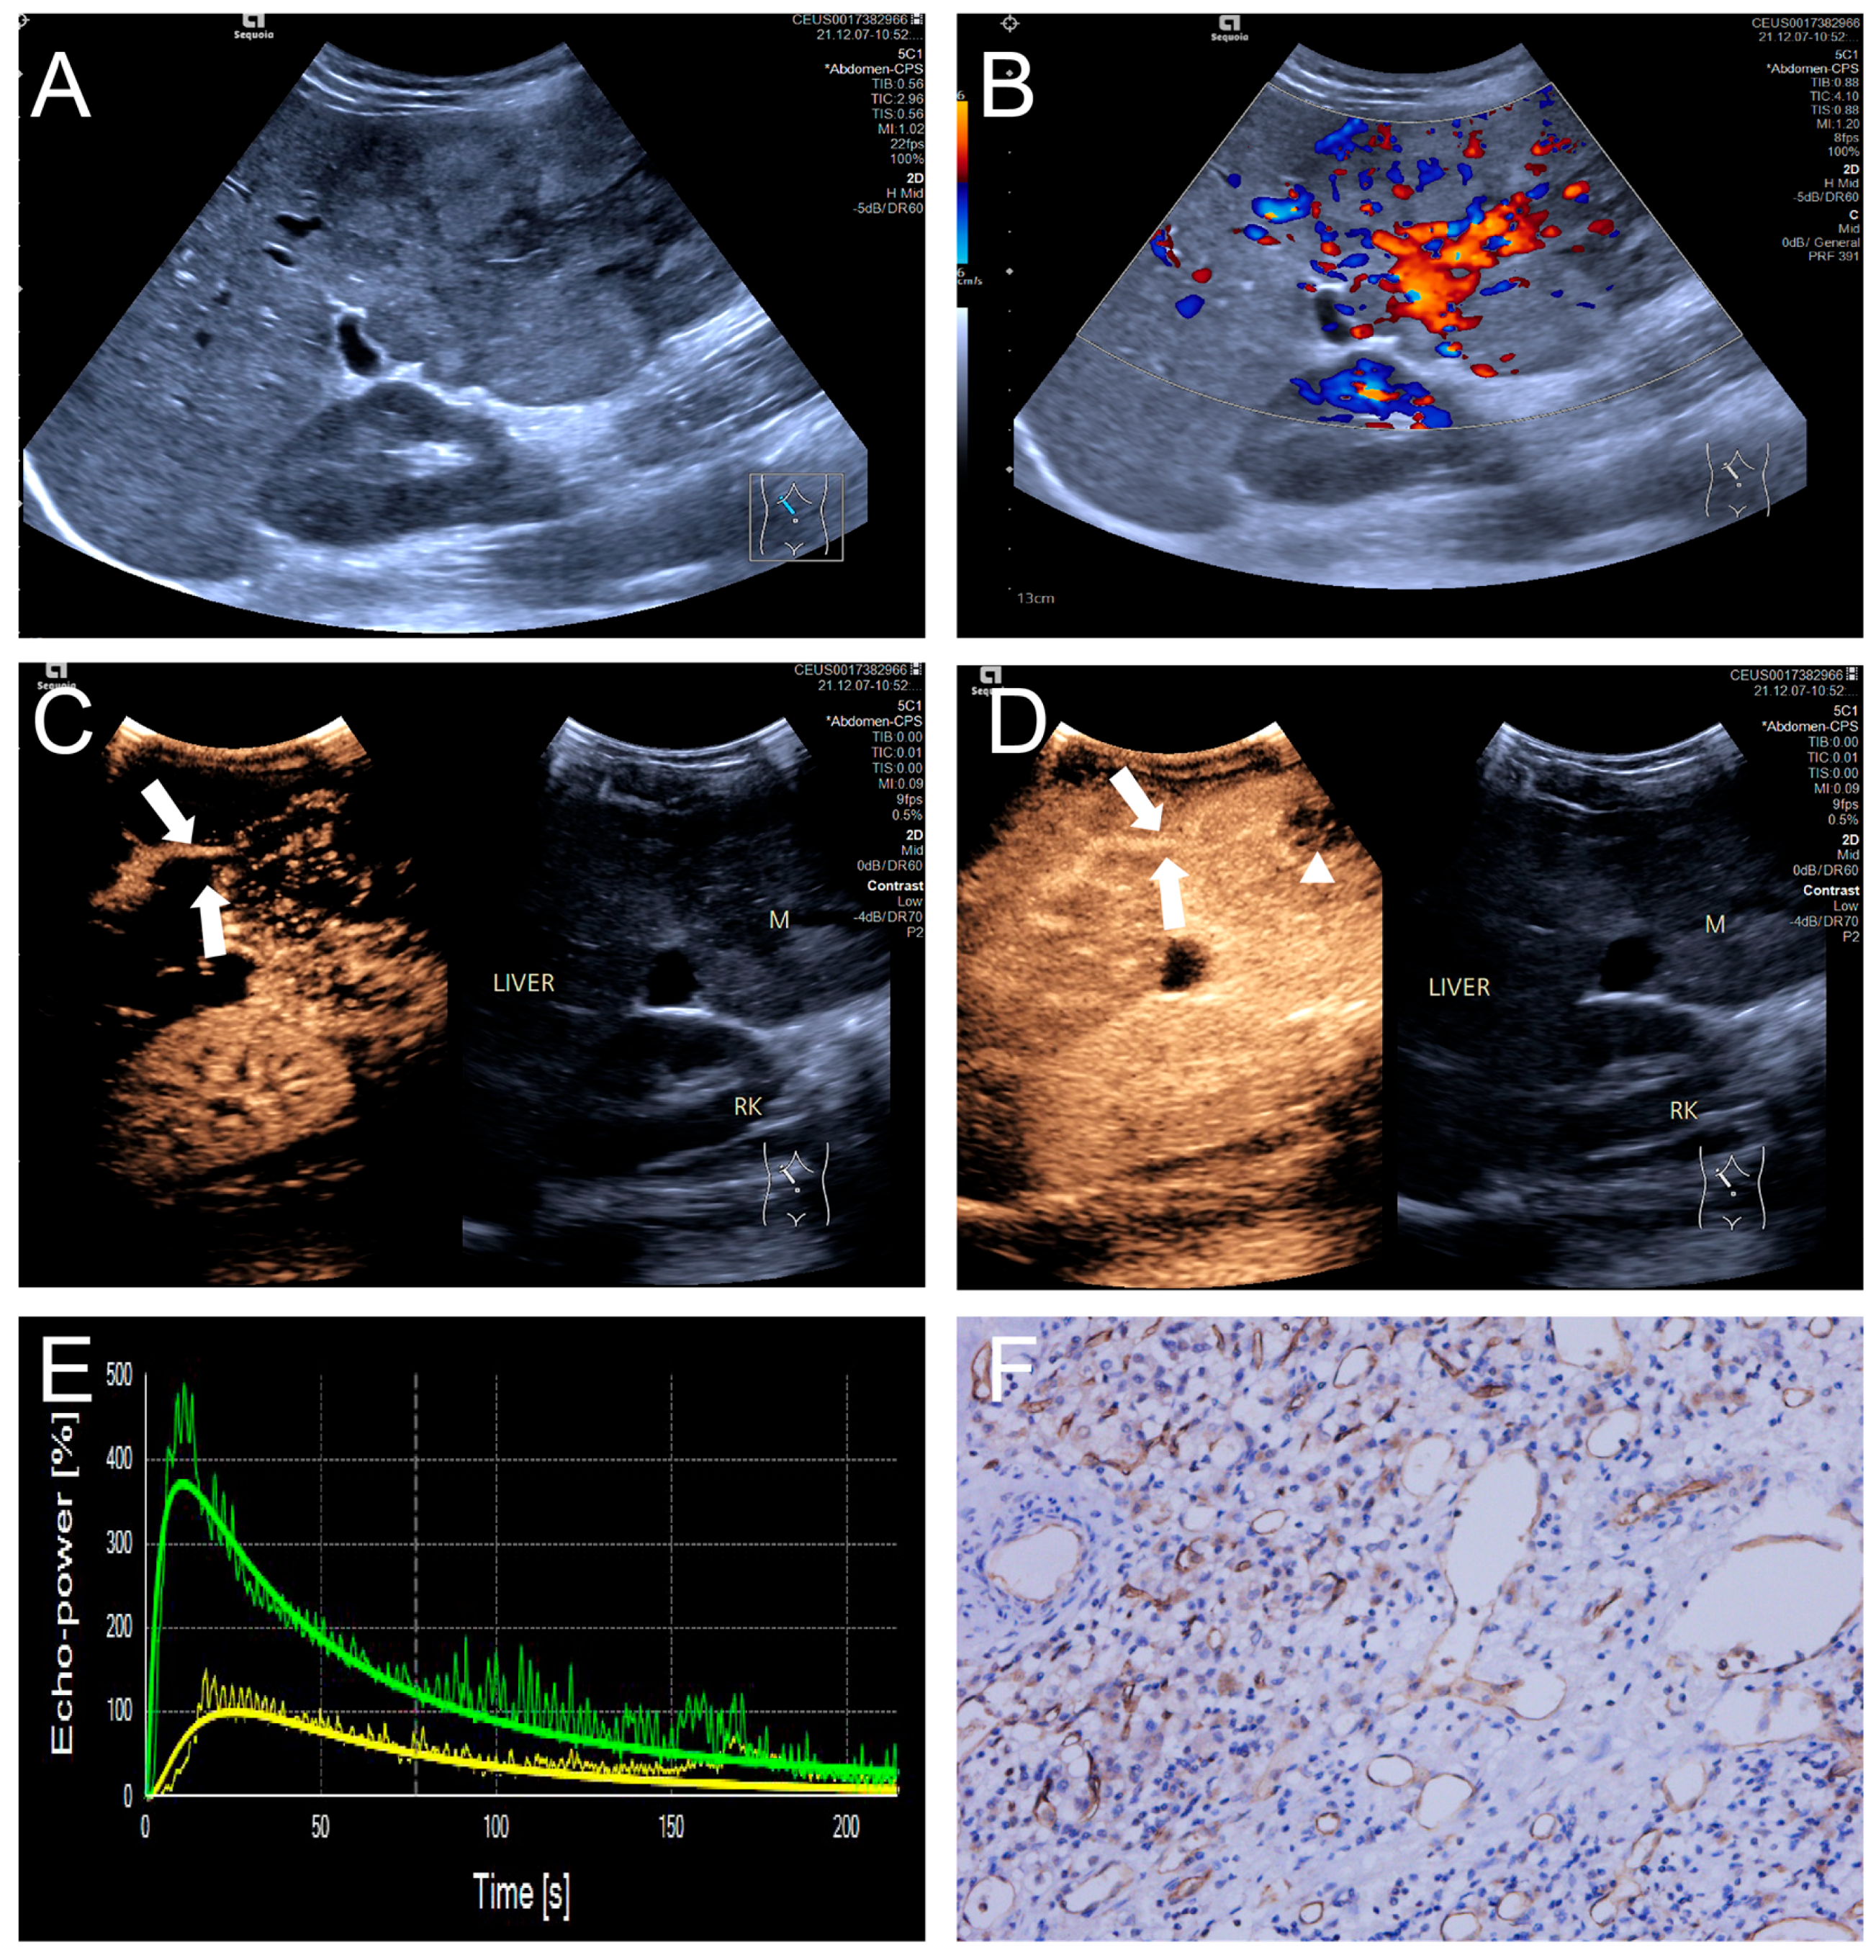

Figure 4.

(A–F) A male patient aged 10 years and 6 months with HB and high MVD. (A) The imaging revealed a lesion with unclear margins and hyperechoic echogenicity in the liver’s left lobe; (B) During the enhancement phase, CDFI revealed abundant vascular signals within the tumor tissue, classified as grade III by Adler; (C,D) The CEUS exhibited non-uniform enhancement progressing from periphery to center, with non-enhancing regions (triangles) within the lesion and peripheral penetrating vessels (arrows); (E) TIC curves showed contrast enhancement of the lesion (green) and perfusion of the adjacent liver parenchyma (yellow). Jagged lines indicated raw signal data, and smooth lines indicated the fitted curves; (F) The biopsy specimen’s cytological immunohistochemical staining revealed dense microvessels (CD34 staining × 200), and the MVD measured 42 lines/HPF.